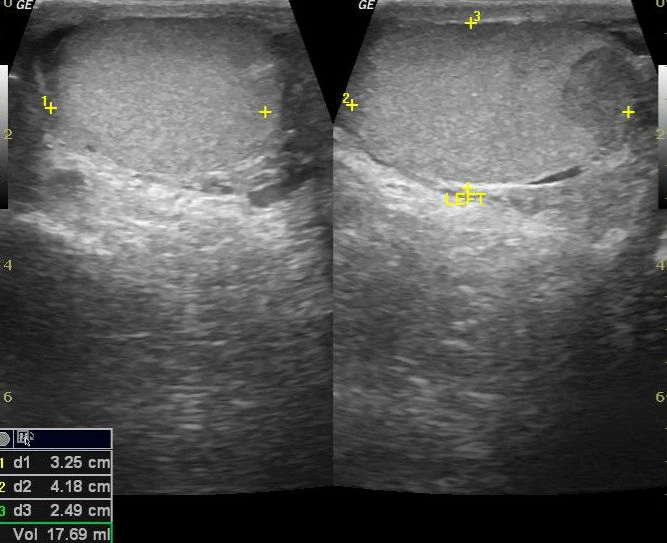

• Tổn thương một bên

Xoắn tinh hoàn (Testicular torsion)

Viêm tinh hoàn (Orchitis)